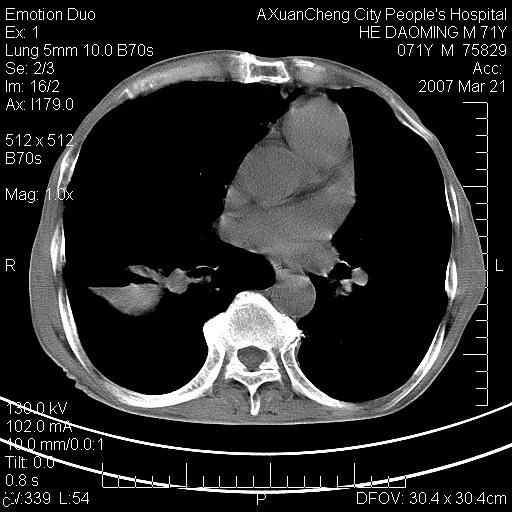

标题: CT7269:[原创] 咳嗽,咳痰,大家讨论右肺病变的部位 [打印本页]

标题: CT7269:[原创] 咳嗽,咳痰,大家讨论右肺病变的部位

右侧相当于叶间软组织样密度ct值约50hu,请大家讨论是什么性者病变

右下肺大囊肿伴感染.肺气肿,肺大泡.

考虑:慢性支气管炎合并全小型肺气肿、肺大泡、间质纤维化、感染,右斜裂积液。

考虑慢支,肺气肿,肺大泡,间质纤维化;右侧斜裂液气胸考虑(可能因为肺大泡破裂破入斜裂所致).

考虑:慢性支气管炎合并右侧全小型肺气肿、肺大泡并感染、双肺间质纤维化,右斜裂积液。

如果患者变化一下体位扫描可分辨液平与斜裂的关系。

考虑:慢性支气管炎合并右侧全小型肺气肿、肺大泡并感染、双肺间质纤维化,右斜裂积液。右侧斜裂液气胸考虑(可能因为肺大泡破裂破入斜裂所致).